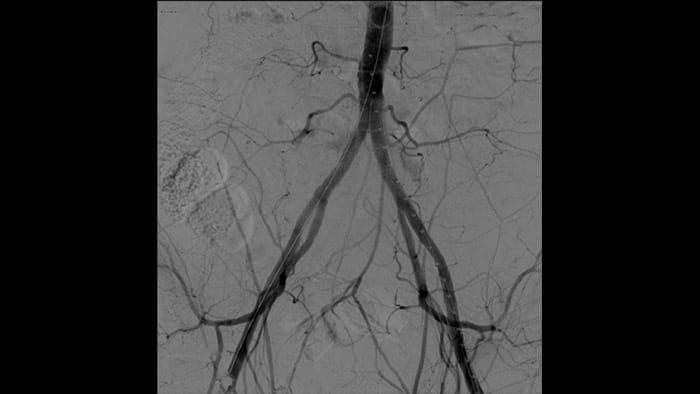

With the Philips Zenition mobile C-arm, Dr. Vila is obtaining outstanding high-quality images that allow him to perform most vascular procedures at the low dose setting.

With the Zenition, our DSA image quality has improved greatly. We no longer see a grainy image. We just see a very clear image."

Dr. R. Vila, MD

Bellvitge University Hospital, Barcelona, Spain

Digital subtraction angiography (DSA) is used in interventional vascular procedures to clearly visualise blood vessels by removing structures that can obscure vessel visibility. Roadmap fluoroscopy overlays a previously acquired subtracted contrast image on the live fluoroscopy, allowing you to track a device without reinjecting contrast.